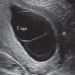

Guida al Counseling: cisti ovariche benigne

vi presentiamo la seconda guida al counseling del 2022 relativa alle cisti ovariche benigne. Potrete scaricarla cliccando sul link.